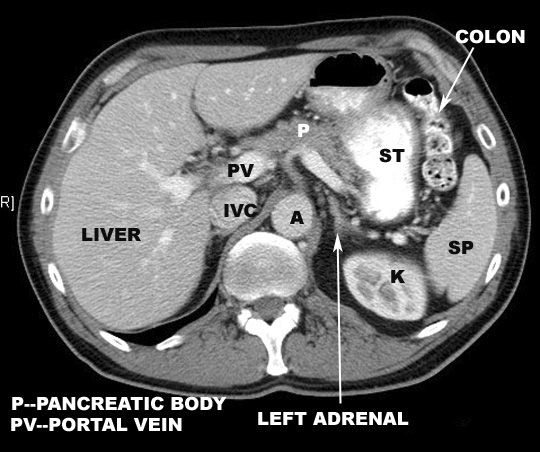

Lies crosswise in the abdominal cavity

in the left hypogastric and epigastric regions beneath the

diaphragm.